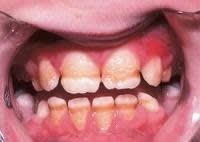

2/ FLUOROSE

PRÉVALENCE : 1 à 5% en France.

ASPECT CLINIQUE :

- Opacités blanches (cas légers) à brunes (sévères) dessinant des lignes horizontales suivant les périkymaties. Ces lignes sont parfois fusionnées dessinant alors plutôt des amas/tâches.

- A l'opposé d'une MIH, l'atteinte est bilatérale et symétrique. Toutes les dents sont atteintes.

- Les contours des opacités sont diffus.